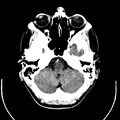

تصوير مقطعي حاسوبي

التصوير المَقْطَعي الحاسوبيX-ray computed tomography نظام تصوير بالأشعة السينية، يُسْتخدم لتصوير مختلف أجزاء الجسم مثل الرأس والقلب والبطن. ويستعين الأطباء بالتصوير المقطعي الحاسوبي على تشخيص الأمراض وعلاجها. وتسمى هذه التقنية أيضًا التصوير المقطعي المحوسب أو التصوير المقطعي المحوري المحوسب.

معرض الصور